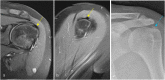

The rotator cuff is a group of four muscles and tendons surrounding the shoulder joint providing it strength and stability. The rotator cuff consists of the subscapularis, supraspinatus, infraspinatus and teres minor. Many shoulder complaints are caused by rotator cuff pathology such as impingement syndrome, tendon tears and other diseases e.g. calcific tendonitis. Diagnosis starts with clinical history and physical examination, after which imaging is often used to help confirm clinical findings depending on the differential diagnosis. The aim of the article is to review the frequently used imaging modalities to assess the rotator cuff and cuff-related disease, specifically focusing on radiography, ultrasonography and magnetic resonance imaging. This article will outline the advantages and disadvantages for each modality and illustrate typical radiological findings of common rotator cuff pathologies.